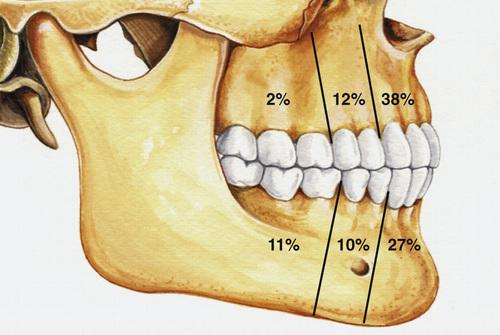

What are the three different clinicoradiographic presentations of ameloblastoma?

- conventional solid or multicystic (80%)

- unicystic (18%)

- peripheral or extraosseous (2%)